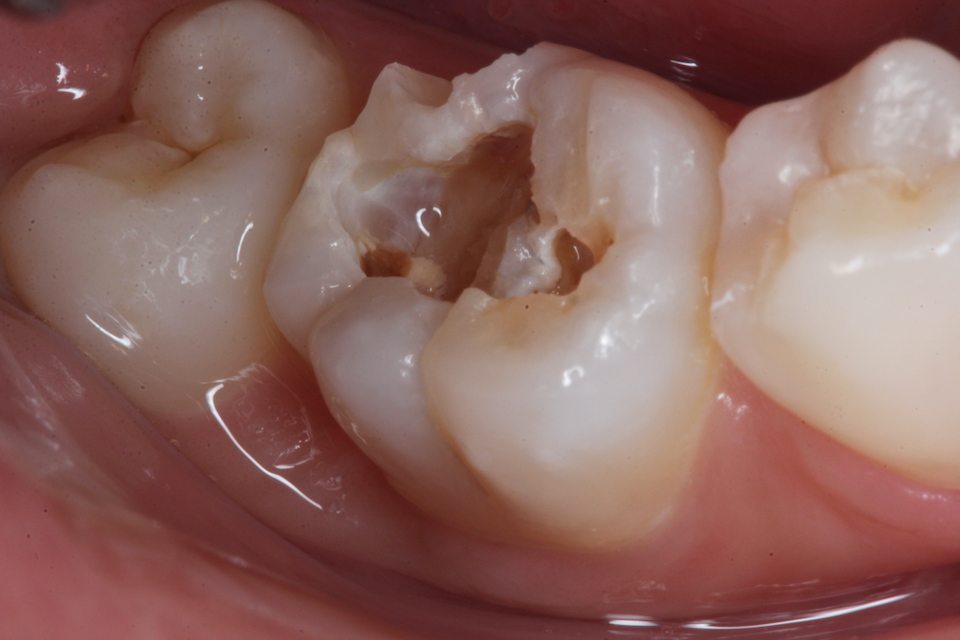

通常の歯科治療では神経を取って被せるということになるのだが、2次象牙質もできていて痛みもないのでそのままCRで再建した。

この方がトータルでは歯の寿命は長くなる。神経を取った歯は10年〜50年後には抜歯になってしまう。治療が上手くいっていても平均30年位か?

CR充填再建過程